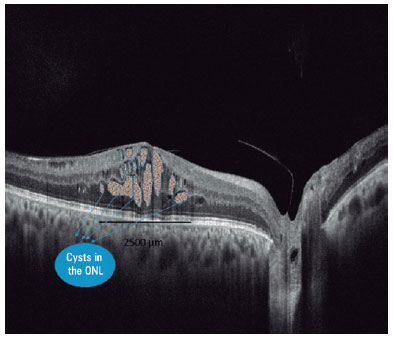

The best-corrected visual acuity (BCVA) was measured decimally at each visit and converted to the logarithm of minimum angle of resolution (logMAR) of the visual acuity. All SD-OCT images were imported into Image-J software (Fiji, NIH, Bethesda, MD, USA) for image processing(14). All cysts were traced manually with the polygon tool option. The total area covered by the cystoid spaces in the area of 2500 micrometer diameter, including the fovea and parafovea, was measured (Figure 1). The baseline average reflectance values of the cystoid spaces were measured as described previously(15). We further quantified the reflectivity levels of the vitreous cavity and nerve fiber layer as the internal standard in each image. The relative OCT reflectivity value of the cystoid spaces was calculated as an arbitrary unit according to the formula:

At the final visit, 18 eyes (50.0%) had at least two lines of improvement in BCVA. There was no difference in the initial total cyst area between successful and unsuccessful eyes in terms of visual acuity (p=0.498). The improvement in visual acuity was more limited in eyes with a cystoid space in the outer nuclear layer (ONL) (p=0.015). Intracystic reflectivity was higher in eyes with poor BCVA than in eyes that had good vision after three injections (p=0.028). The rates of EZ defect and presence of DRIL were higher in the group with poor visual acuity (p=0.019, p=0.011, respectively). No difference was noted in the presence of TPHM, presence of subretinal fluid, and number of HRF between eyes with poor and better vision. Table 2 shows the comparison of the eyes with poor and better BCVA.

Of the 36 eyes, 22 had cysts in the ONL. While 13 (59.0%) of 22 eyes with a cystoid space in the ONL had EZ disorder, only 1 (7.1%) of 14 eyes without cystoid space in the ONL had EZ disorder (p=0.009). In eyes with cysts in the ONL, the presence of DRIL was noted in 15 of 22 eyes (68.1%), 2 of 14 (14.2%) eyes without ONL cysts had DRIL (p=0.013).

Large ONL cysts are seen in the later stages of DME and negatively affect macular function(24). In this study, a relationship was noted between the extension of cystoid spaces and photoreceptor damage. In addition, no relationship was found between the size of the cyst and visual results, but visual success was low in patients with ONL cysts. EZ damage was more extensive in eyes with ONL cysts. The rate of DRIL was also higher in eyes with ONL cysts. Is this effect of cysts caused by mechanical compression? Or are there other underlying pathophysiological mechanisms? The cystoid spaces primarily start in the inner layers, so the presence of an ONL cyst can give information about the onset of the pathology. Here, the negative effect of long-term edema on Muller cells, as a result of the disrupted glutamate uptake by Muller cells, and the neurotoxic effect of extracellular glutamate toxicity should be questioned. Accordingly, the rate of DRIL in those with ONL cysts was higher than in those without external cysts. This implies that the presence of ONL cysts indicates further damage in the inner layers. To understand this issue better, the presence of a relationship between the characteristics of cysts in eyes with cystoid formation and the health of intraretinal neurons should be examined.